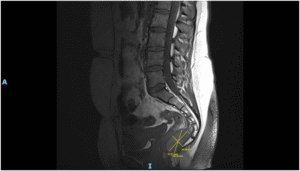

Imaging via MRI and CT demonstrated a complex, encapsulated lesion with peripheral enhancement and restricted diffusion. Multidisciplinary evaluation suggested a congenital epidermoid or duplication cyst. Given the absence of malignancy and surgical complexity, a conservative management strategy was adopted.

Figure 1: Figure 1 Duplication cyst 2025 MRI sagittal plane

Figure 2: Figure 2 Duplication cyst 2025 MRI sagittal plane